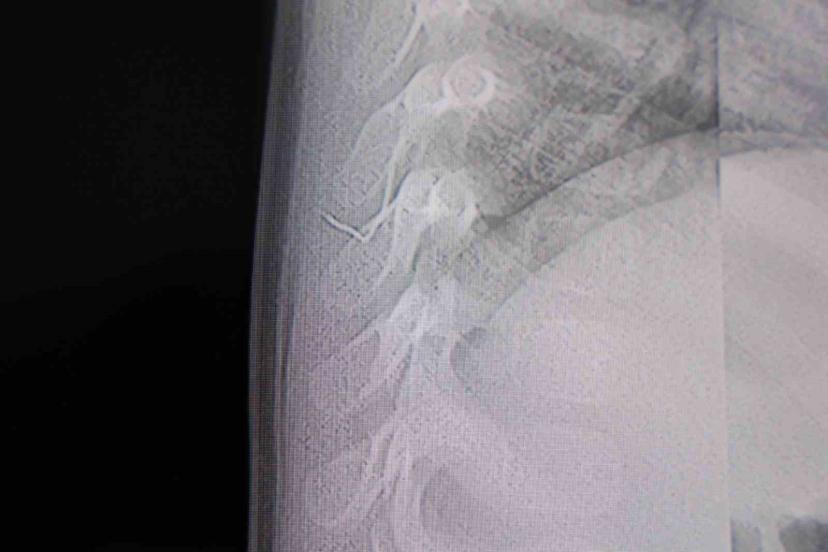

Kahramanmaraş’ta sırt üstü yatmak istemeyen, yatırıldığında ağlama ve huzursuzluğu nedeniyle hastaneye götürülen bir yaşındaki bebeğin sırtından akciğer zarına doğru ilerleyen 2 santimetrelik zımba teli çıktı.

Alınan bilgiye göre, Kahramanmaraş’ta farklı ortopedi, çocuk cerrahisi ve beyin cerrahisi kliniklerine başvurusu yapılan bir yaşındaki bebeğin, sırt bölgesinde yabancı bir cisim olduğu ancak müdahalenin zor olduğu ve 8 yaşına kadar beklenmesi gerektiği bildirildi. Aile, bebekleri için son olarak HG Hospital’e başvurdu. HG Hospital Beyin ve Sinir Cerrahisi Uzmanı Prof. Dr. İdris Altun tarafından yapılan tetkiklerde, yabancı cismin cilt altında, omurilik kanalına yakın bir bölgede olduğu ve akciğer zarına doğru ilerlediği belirlendi. Hasta, genel anesteziye alınmadan, lokal anestezi ve sedasyon eşliğinde ameliyata alındı. Yapılan müdahalede yabancı cisim tamamen çıkarıldı. Çıkarılan cismin, ince zımba teline benzer metal bir tel olduğu ve yaklaşık 2 santimetre uzunluğunda bulunduğu tespit edildi. Hasta, aynı gün taburcu edildi.